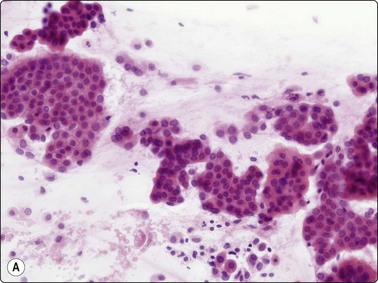

image image

Fig. 8.18 Adenocarcinoma, well differentiated

(A) Monolayered sheets and papillaroid clusters of glandular cells (H&E, HP); (B) 3-D clusters and a sheet of glandular cells with a palisaded edge (H&E, HP). Diagnosis of malignancy based on abundance of material and complex architecture.

Fig. 8.19 Adenocarcinoma

(A) Monolayered sheet of glandular cells showing enlarged hyperchromatic nuclei with irregular outlines and several intranuclear cytoplasmic inclusions (H&E, HP). (B) 3-D clusters of glandular cells (MGG, HP). Inset: intranuclear cytoplasmic inclusions (MGG, HP oil).

The cellular morphology of adenocarcinoma is similar to that described in brush material. Rosettes, acinar formations or cohesive cell clusters (Figs 8.18 and 8.19) represent anatomical structures removed from the tumor by the needle. The larger the gland formations, the less likely they are to be removed intact and, when only partly removed, deposit on the slide as flat sheets in a monolayer (Fig. 8.18): a useful indicator of glandular differentiation. Artifactual spaces are often seen in large tissue fragments and may be misinterpreted as acinar structures; however, where the spaces have an ‘anatomical’ rigidity, they may indicate glandular differentiation. Mucin secretion is difficult to identify without the aid of special stains, and vacuolation of the cytoplasm may occur as a result of degeneration or the presence of glycogen. In H&E- or Pap-stained material vacuoles with a central, inspissated, eosinophilic or orangiophilic center are very suggestive of mucin secretion and correspond to the intracellular lumina described ultrastructurally in adenocarcinomas. With MGG staining, mucin may be visible as magenta or purple material within the cytoplasm, either homogeneously or as red granules within a pale vacuole. Well-formed columnar cells or groups of palisaded cells may be a guide to glandular differentiation and terminal plates/bars may also be present. In the 2004 WHO classification,217 the definition of BAC was limited to a non-invasive process and is now an uncommon diagnosis, requiring full histological assessment; there is currently debate as to whether the term should be used at all, especially since a diagnosis of BAC cannot be rendered on small biopsy samples or cytological samples. However, it is still possible to suggest that a tumor may have a BAC-like component based on cytological features. These include large, cohesive, monolayered sheets which reflect the growth of neoplastic cells in a monolayer along alveolar walls, papillary processes, cell balls and clusters, intranuclear cytoplasmic inclusions and psammoma bodies (Figs 8.18-8.22). The radiogical appearance of a purely ground-glass opacity without a solid component is also suggestive of a BAC.